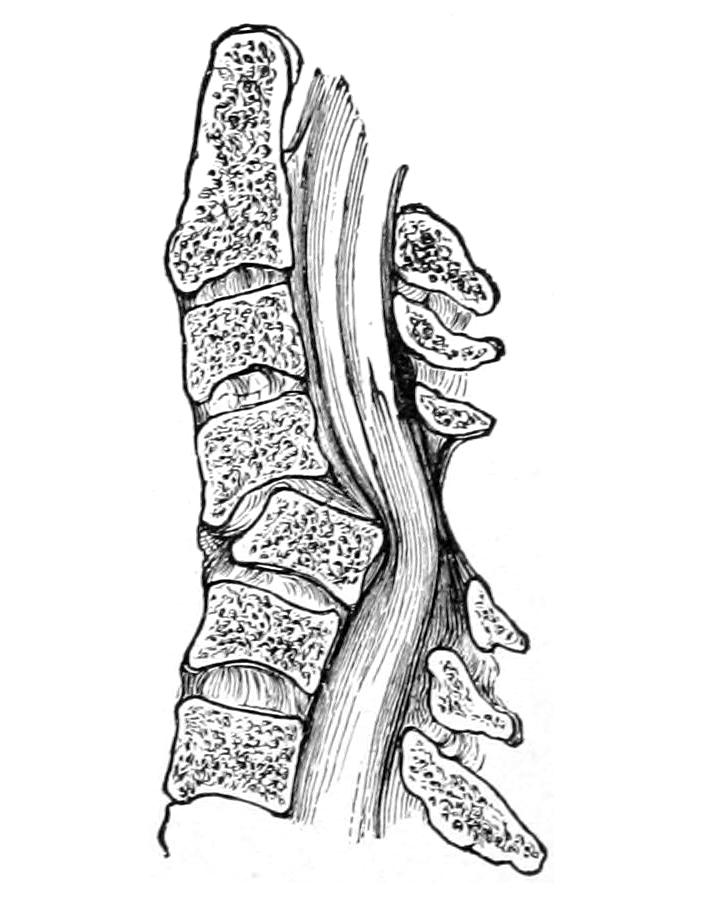

CHAPTER XXXVIII.

THE SPINE, THE SPINAL CORD AND THE PERIPHERAL NERVES 621